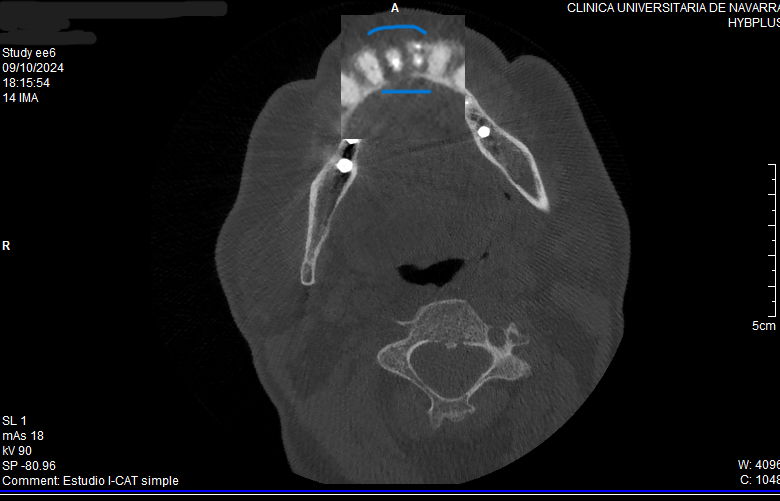

Tras realizar un diagnóstico por imagen en 3D, observamos la pérdida total de la cortical vestibular y lingual a nivel del 4.1 (Figura 7 -8).